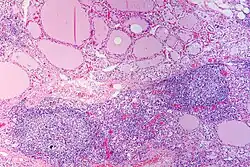

Endgültige Sicherheit bringt die histologische (feingeweblich-mikroskopische) Untersuchung von Schilddrüsengewebe, das mittels einer Feinnadelpunktion gewonnen wurde. Bei der Hashimoto-Thyreoiditis erkennt man neben anderen Kriterien vor allem ein dichtes Infiltrat von Lymphozyten und auch Lymphfollikel (siehe Abbildung), die Ausdruck der entzündlichen Vorgänge sind.